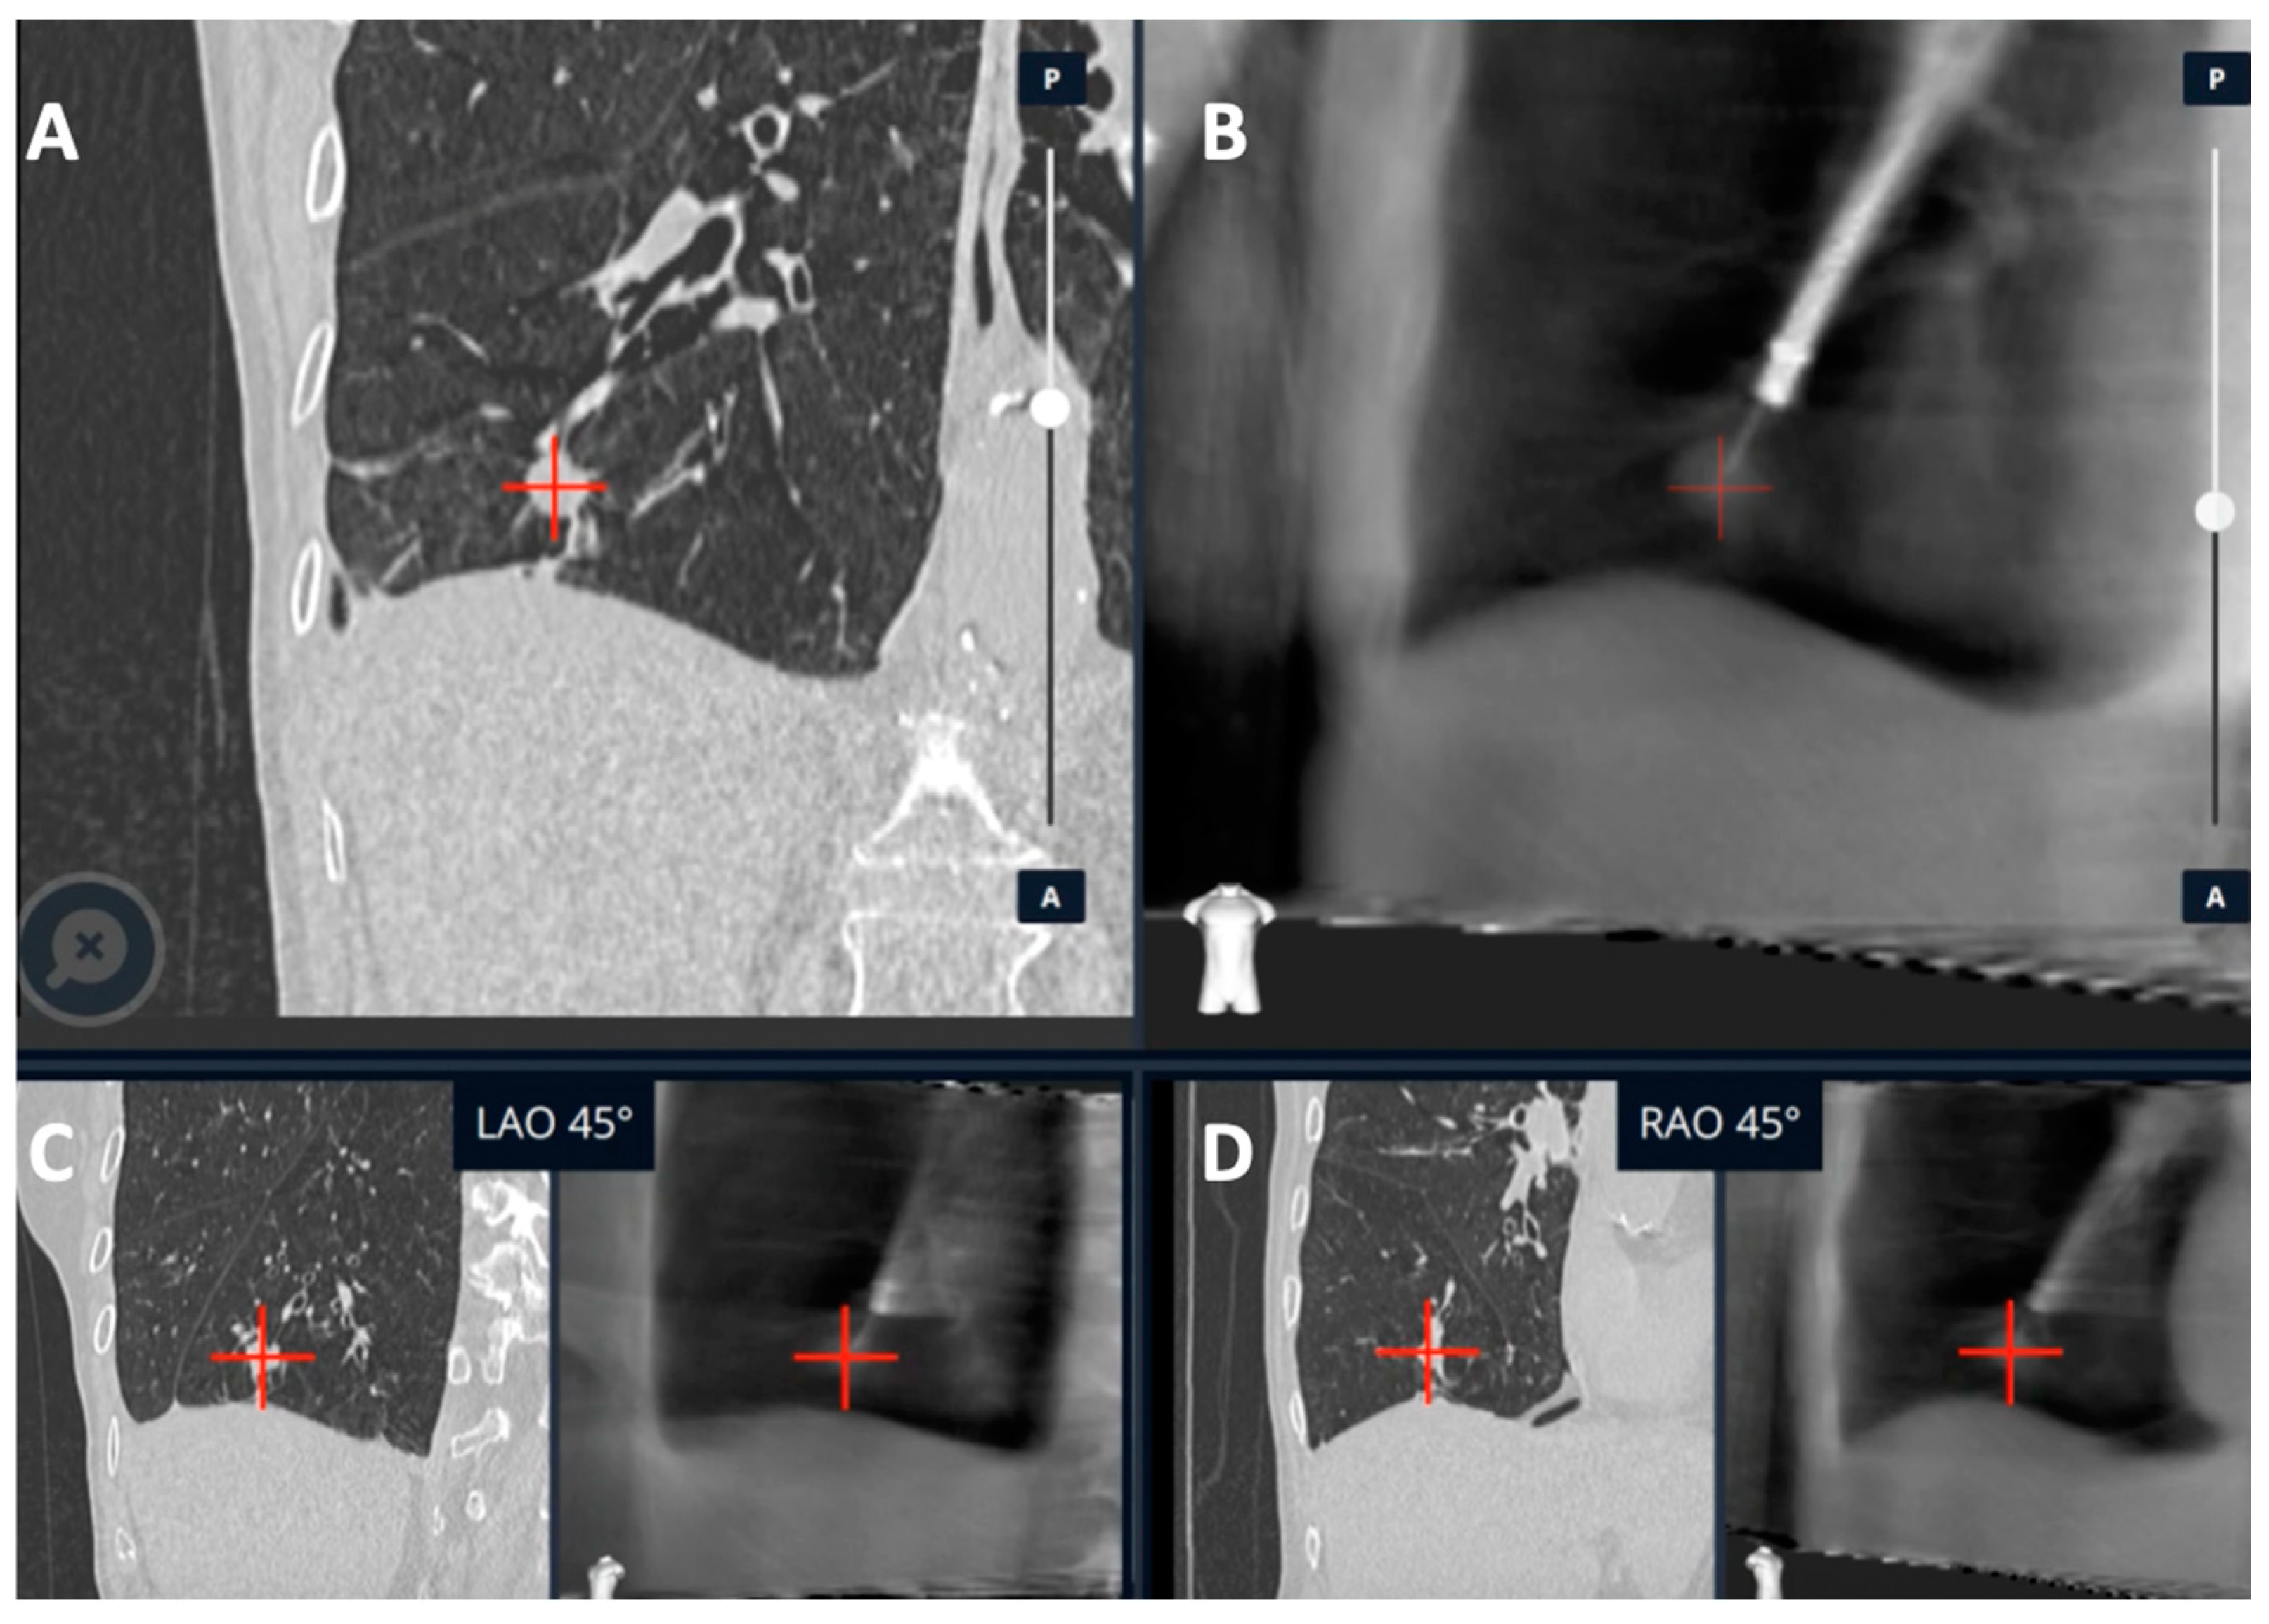

- Kalchiem-Dekel, O.; Fuentes, P.; Bott, M.J.; Beattie, J.A.; Lee, R.P.; Chawla, M.; Husta, B.C. Multiplanar 3D fluoroscopy redefines tool-lesion relationship during robotic-assisted bronchoscopy. Respirology 2021, 26, 120–123. [Google Scholar] [CrossRef] [PubMed]

| Kalchiem-Dekel et al. [20] | Ion™ robotic platform with CIOS | Robotic platform for navigation with 3D multiplanar fluoroscopy for intra-procedural real-time guidance | 10 lesions | Tool in lesion: 90%. Tool correction in 30% lesions with real-time imaging. DY not reported | - |

| Reisenauer et al. [11] | Ion™ robotic platform with CIOS | Robotic platform for navigation with 3D multiplanar fluoroscopy for intra-procedural real-time guidance | 30 lesions | DYi: 93%. Average divergence: 10 mm in upper lobe 20 mm in lower lobe | No adverse events |